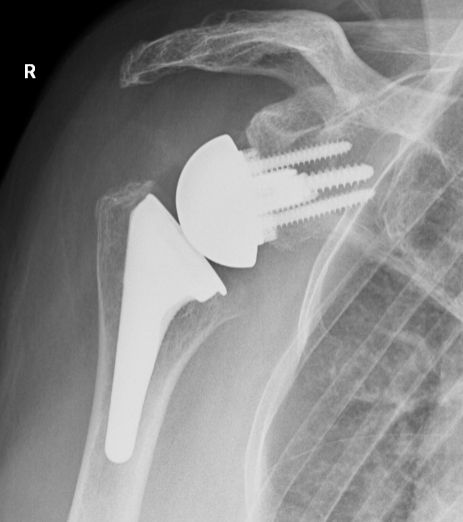

Reverse